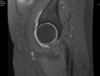

MR-arthrogram

Superior Cam Lesion

Retroversion with large pincer

Tonnis grade 1 (no cysts)

greater than 2mm joint space

moderate osteoarthriis

The labrum demonstrates some anterosuperior degenerative blunting but otherwise maintains its normal triangular morphology. There is moderately advanced anterosuperior joint space narrowing and cartilage loss consistent with osteoarthritis.

The morphology of the femoral head and neck are unremarkable and there are no findings to suggest femoroacetabular impingement.

Findings are compatible with right hip osteoarthritis, concordant with MR arthrogram of right hip on 8/23/2019.